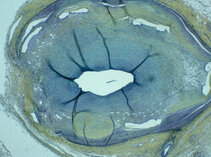

Our research group specializes in molecular and basic science models of clinically relevant topics. Our team is interested, for instance, in developing methods to predict and prevent recurrence of stenotic lesions after catheter interventions.

We have previously evaluated modifications of thrombectomy devices, stents and balloons delivering drugs to the vessel wall, and we have created new methods of ultrasound analysis in vascular medicine.

We are focusing our science momentarily on biocompatibility studies of novel biodegradable and resorbable materials such as biopolymers (i.e. PGLA) or trace elements such as magnesium or zinc potentially useful for the manufacture of vascular stents or stent grafts.

These images tell a story and we will explain it to you…..